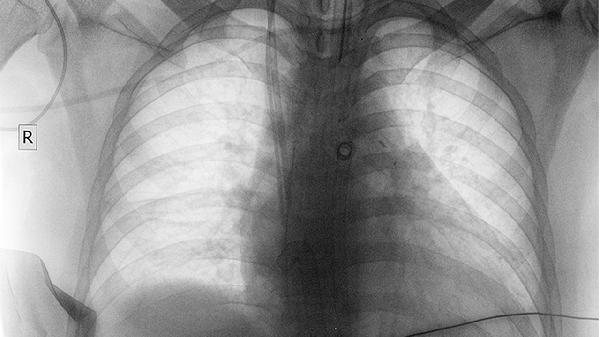

发现纵隔占位或肺部阴影时,应及时进行胸部CT、病理活检等检查明确诊断。日常生活中需避免吸烟及二手烟暴露,注意空气质量,定期体检有助于早期发现病变。确诊后应严格遵循医嘱选择个体化治疗方案,不同性质的肿瘤在饮食调理和康复训练方面也存在差异。